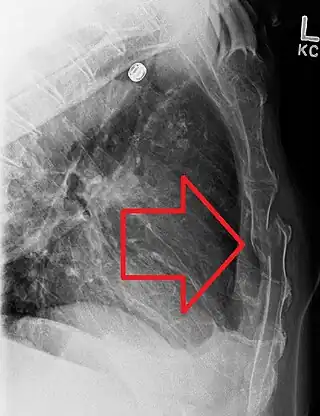

En el diagnóstico se pueden utilizar las manifestaciones clínicas de una fractura, que incluyen: dolor, tumefacción, deformación, equimosis, inestabilidad y crepitación. Para confirmar el diagnóstico, se utilizan dos radiografías en distintos ángulos y TAC ( tomografía axial computarizada ).[5]